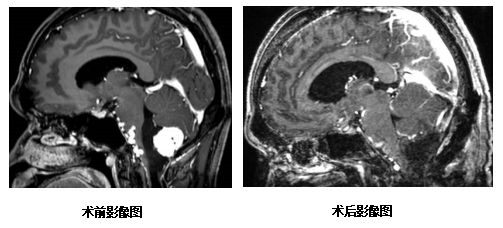

术中肿瘤血供非常丰富,周围被血管、神经包绕,术中止血困难,而且与脑干黏连紧密,分离困难,但陈刚医师手术团队凭借着高超的手术技术和丰富的临床经验,沉着应对,顺利完成手术,最终完整切除肿瘤和畸形血管,完好地保护了脑干和周围正常的血管、神经。

手术虽顺利完成,但术后仍处于危险期,预防并发症的发生仍是一个重要的环节。珠海市人民医院神经外科有专业的神经外科重症监护室及治疗团队,恰好为此类术后重症患者提供安全专业的医疗保障。目前,在医护人员的积极治疗与精心照顾下,麦先生终于安全的度过了术后危险期,吞咽功能较术前明显改善,也没有出现严重并发症,恢复良好。